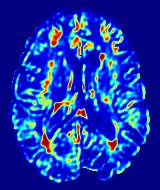

To optimize the membership threshold, we trained a network with patches. Memberships generated on VAL-28 were segmented with thresholds from to with an increment of . The range of Dice coefficients is shown in Fig. 3. The highest median Dice coefficient was observed for a threshold of . This is intuitively reasonable because during training, the lesion memberships of atlases were generated from their hard segmentations using a Gaussian kernel, and it can be shown that the half max of a discrete Gaussian is at .